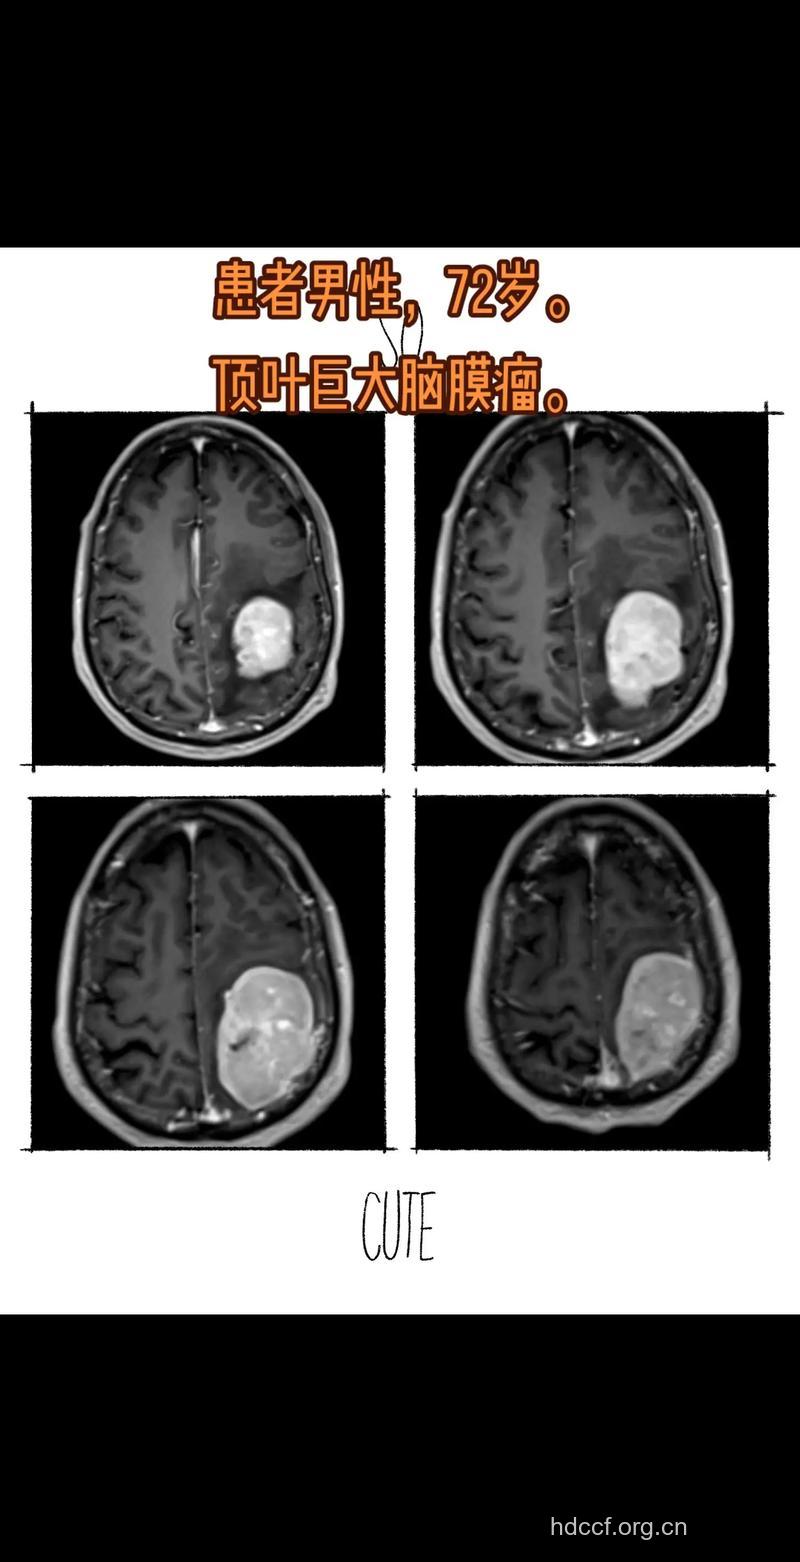

顶叶慢性硬膜下血肿是临床上常见的疾病,以中、青年多见。其临床经过与脑瘤相似,但都有头部外伤史,其伤情多较轻微,故常被病人所遗忘而不主动诉说,甚至追问病史时也记不清。经数月甚至年余才逐渐出现临床症状。早期症状多为头痛、头晕,亦可查出局限性感觉性癫痫或偏身感觉障碍,仔细检查可以发现一些顶叶损害的症状和体征。颅骨平片检查可有慢性颅内压增高表现,通常无骨折线。超声波检查发现中线波移位(双侧性可能无移位)。脑电图检查可有局限性慢波出现。颈动脉造影常示无血管区可明确诊断。